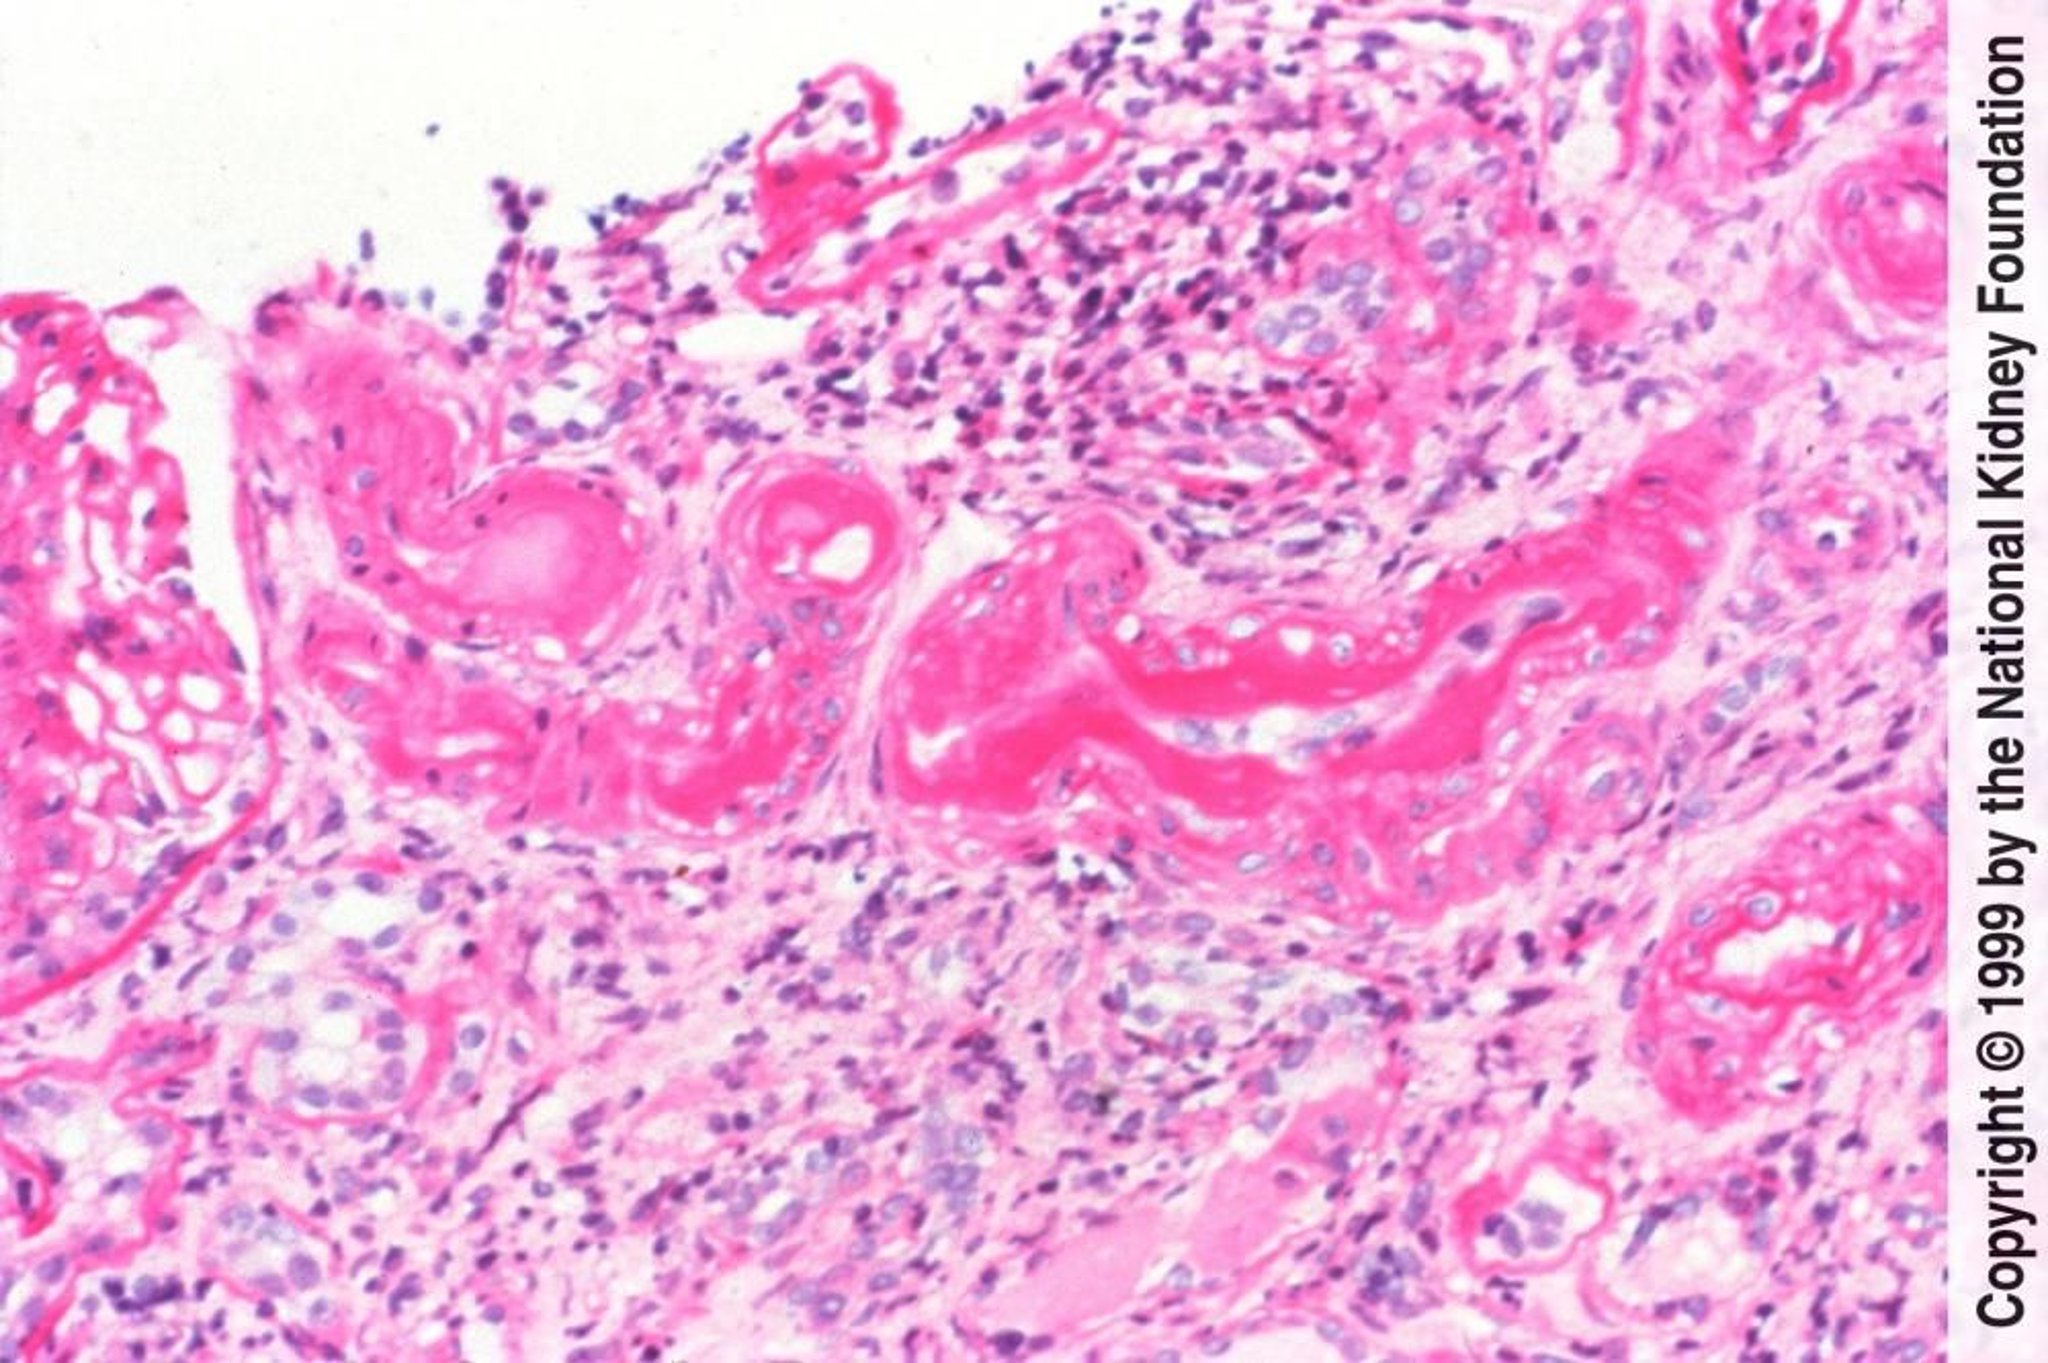

Nefrosclerose arteriolar hipertensiva benigna

A nefroesclerose arteriolar hipertensiva benigna é caracterizada histologicamente por hialinose arteriolar causada por insudação das proteínas plasmáticas e espessamento medial provocado por hipertrofia e hiperplasia das células musculares lisas vasculares (coloração ácido periódico-Schiff, × 200).

Image provided by Agnes Fogo, MD, and the American Journal of Kidney Diseases' Atlas of Renal Pathology (see www.ajkd.org).